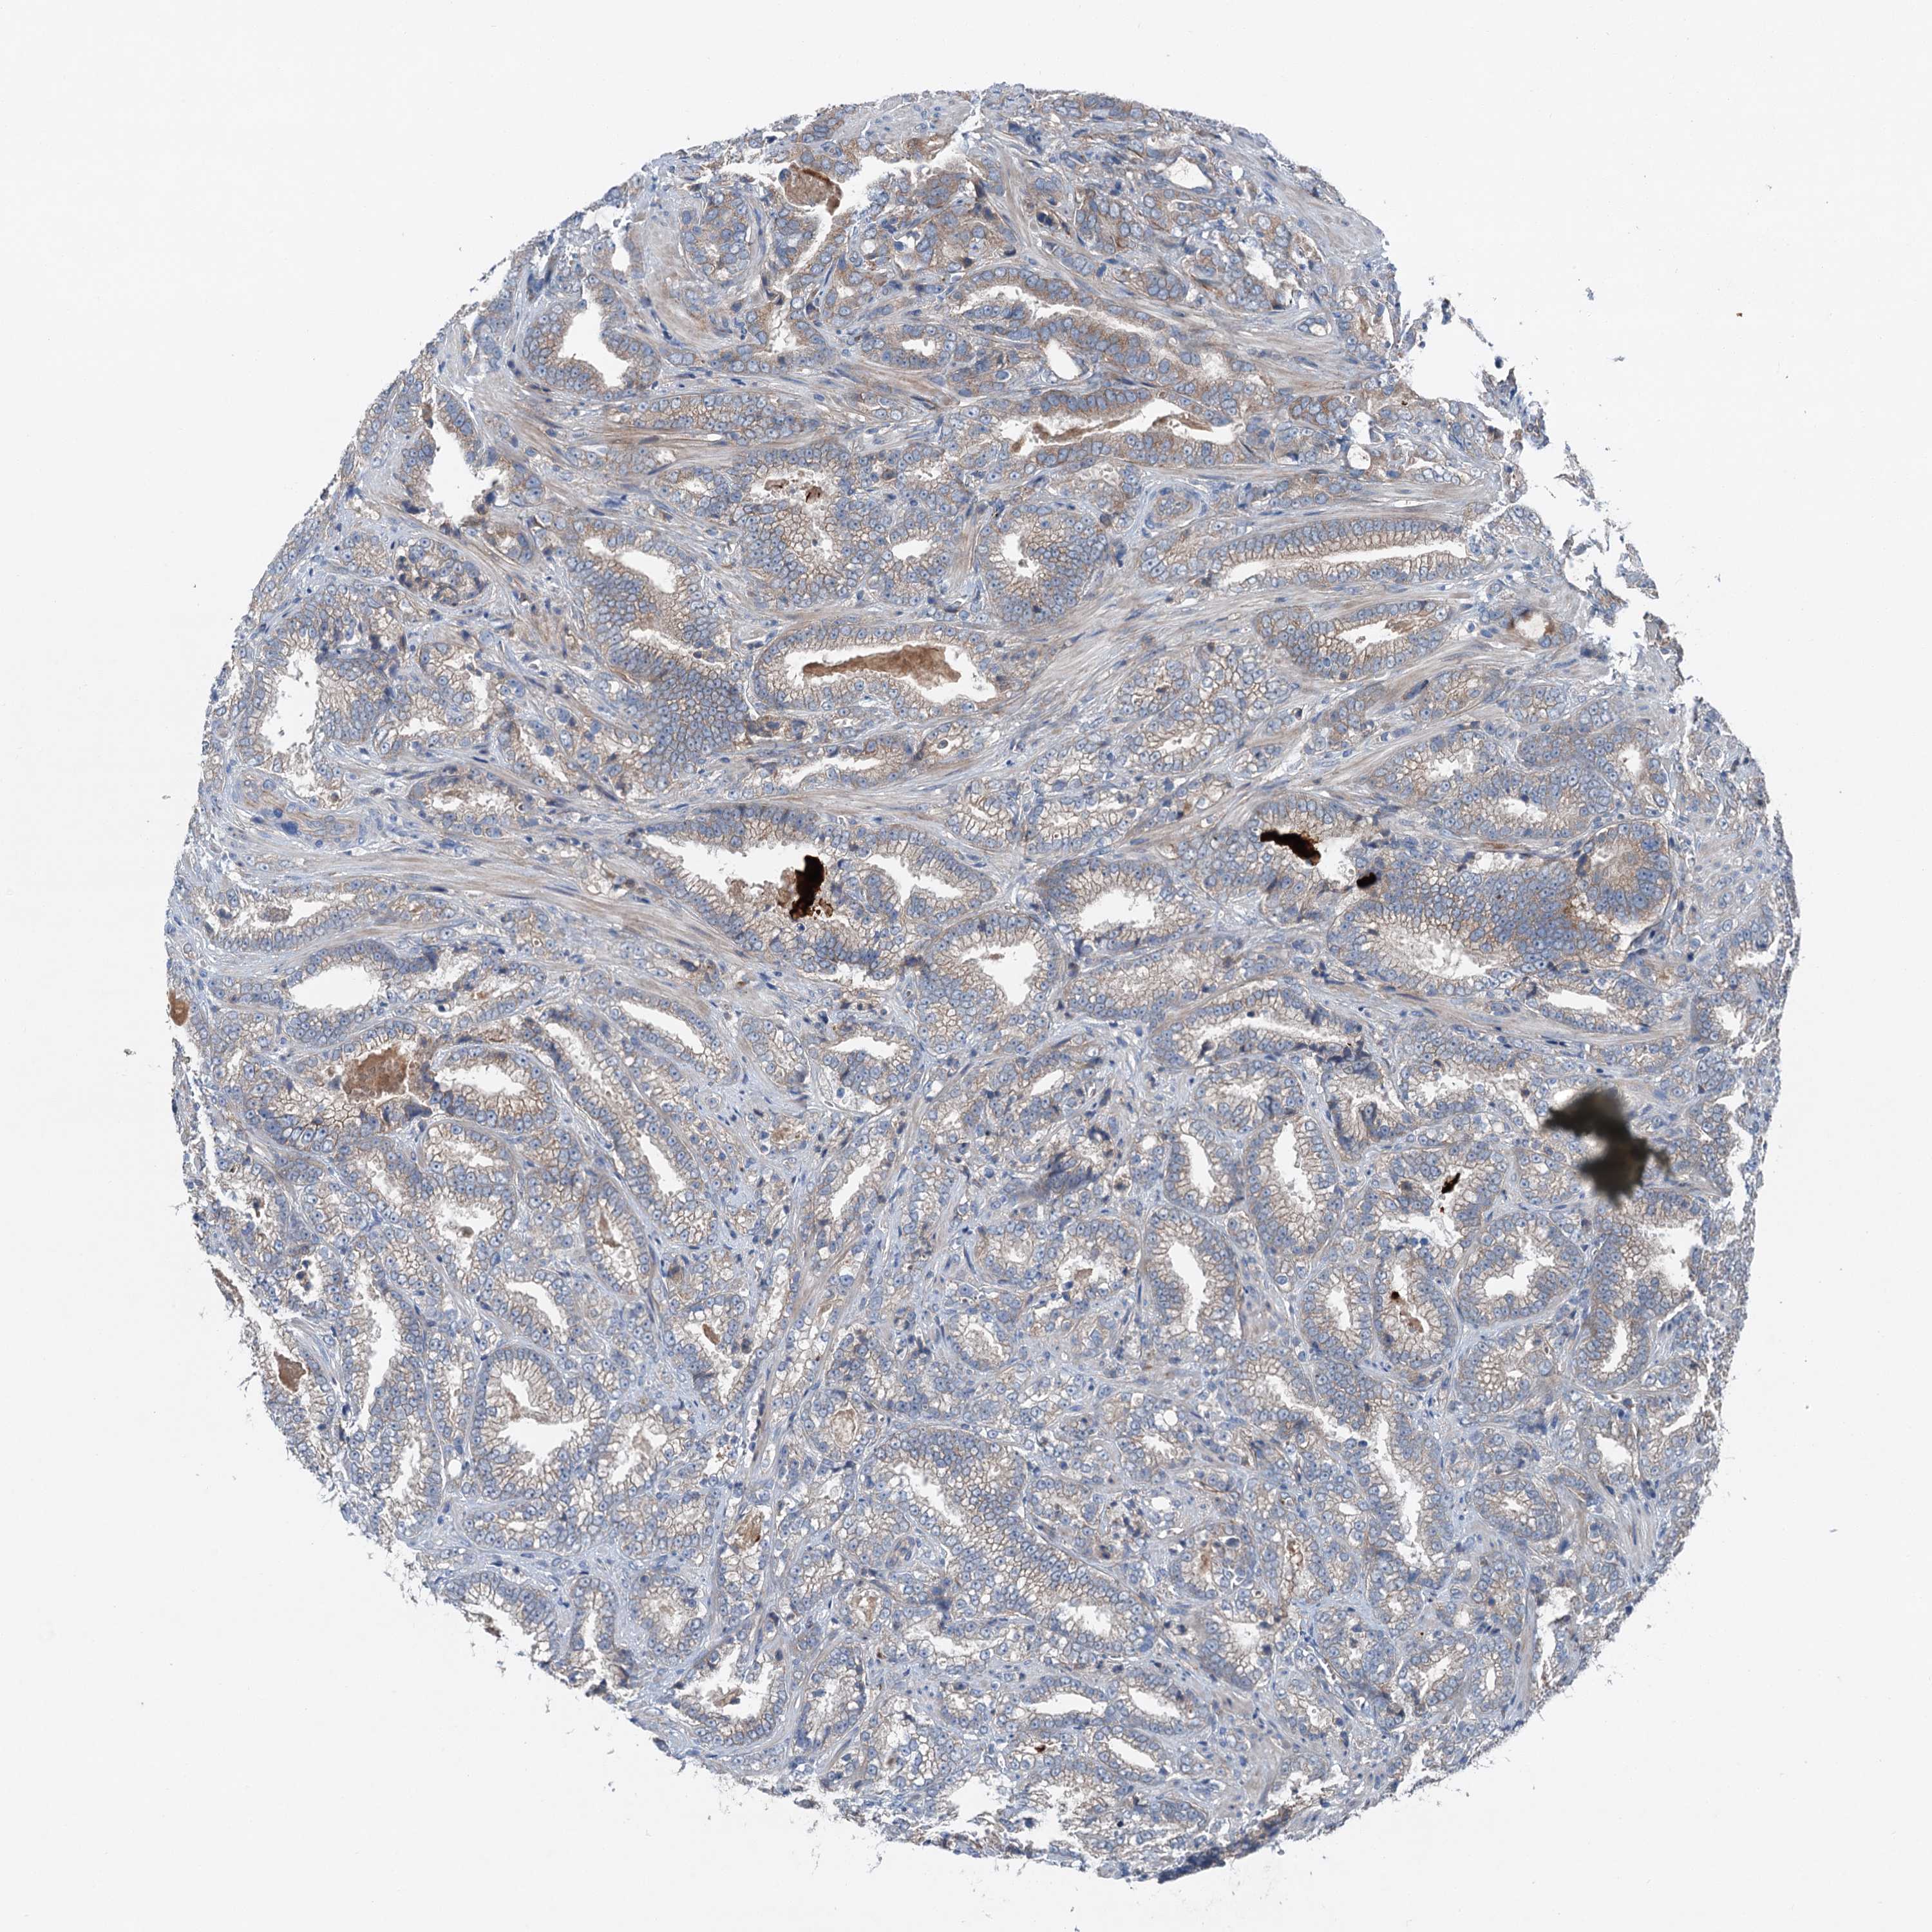

PROSTATE CANCER - Protein expressioni

A mouse-over function shows sample information and annotation data. Click on an image to view it in a full screen mode. Samples can be filtered based on level of antibody staining by selecting one or several of the following categories: high, medium, low and not detected. The assay and annotation is described here.

Antibody stainingi

Antibody staining in the annotated cell types in the current human tissue is reported as not detected, low, medium, or high, based on conventional immunohistochemistry profiling in selected tissues. This score is based on the combination of the staining intensity and fraction of stained cells.

Each image is clickable and will lead to virtual microscopy that enables deeper exploration of all samples and also displays staining intensity scores, fraction scores and subcellular localization as well as patient and tissue information for each sample.

Antibody HPA041015

Staining

High

Medium

Low

Not detected

Intensity

Strong

Moderate

Weak

Negative

Quantity

>75%

75%-25%

<25%

None

Location

Nuclear

Cytoplasmic/membranous

Cytoplasmic/membranous,nuclear

Adenocarcinoma, High grade

Adenocarcinoma, Low grade